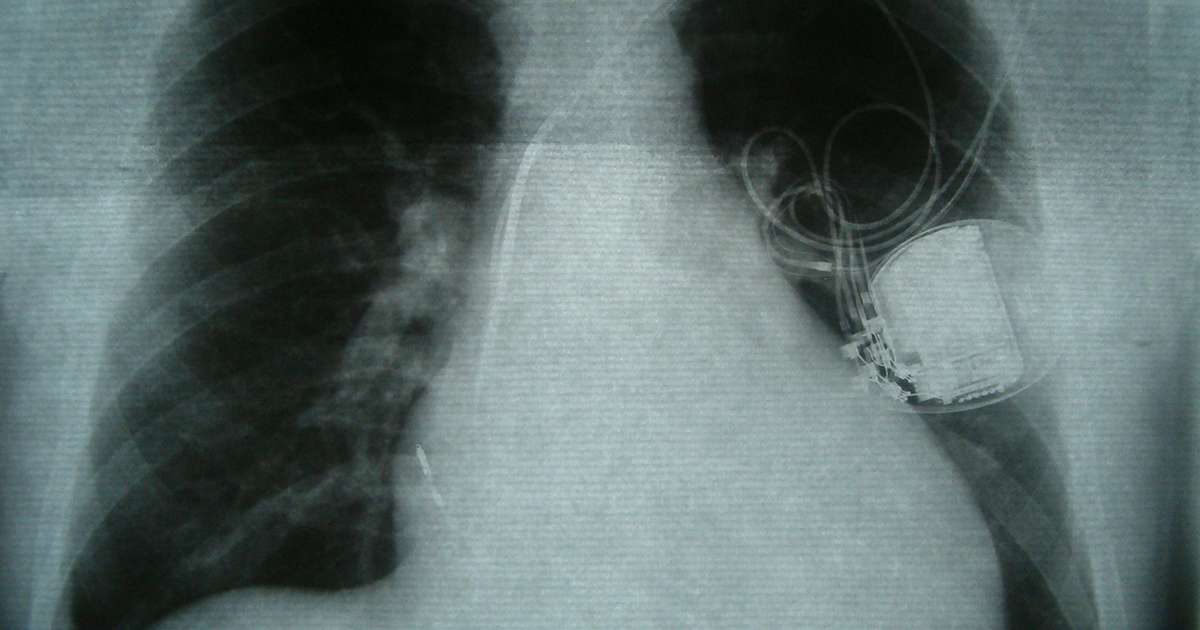

Medical Devices

Most of the medical devices are designed to aid in the control of irregular heartbeats in patients with heart rhythm disorders. There are cardiac electrophysiologists implant devices that either help the hearts electrical system to function properly or measure the heart rhythm. These devices include a pacemaker, implanted under the skin of the chest to produce electrical pulses that keep the heart beating normally and manage the heart rhythm disorders, such as when the heart beats too slowly or beats irregularly. Biventricular pacemakers are implanted if other medications don’t relieve symptoms of heart failure. The other medical device doctors may employ is an implantable cardioverter defibrillator, which helps in shocking the hearts rhythm back to normal for patients with fast irregular heartbeats, called ventricular arrhythmias. The last option is the implantable cardiac loop recorder, which monitors the hearts electrical activity for up to three years before replacement is required.